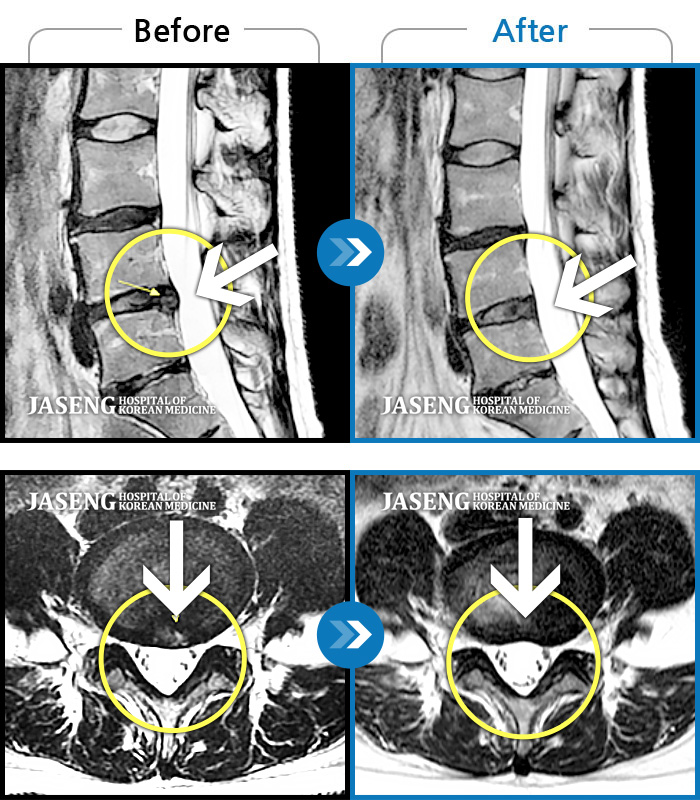

허리디스크

많이 본 사례

강남 · 박종훈 원장

허리와 양쪽 엉덩이 통증 및 좌측 둔부, 대퇴, 소퇴 후면부 통증 및 저림

촬영시기

2013.05.14 ~ 2014.04.23

2014.05.07

조회수 55,357